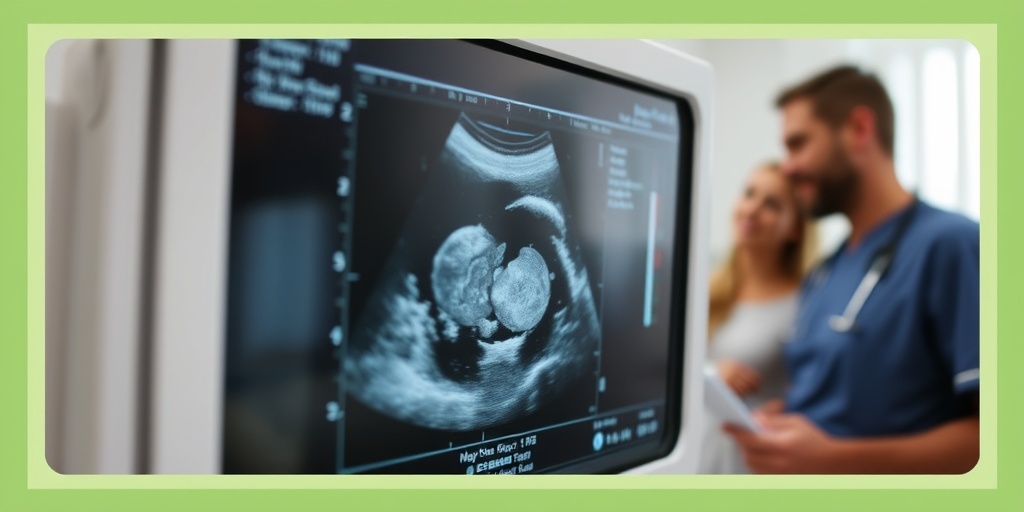

Understanding Ultrasound Images

Ultrasound images can sometimes be confusing, especially for first-time parents. Understanding what you’re looking at can enhance the experience and help you feel more connected to your baby. Here’s a breakdown of how to interpret those early ultrasound images:

1. The Basics of Ultrasound Technology

Ultrasound uses sound waves to create images of the inside of the body. In pregnancy, it allows healthcare providers to visualize the fetus, placenta, and amniotic fluid. The images produced are typically in black and white, with varying shades of gray representing different tissues and structures.

2. Key Features in Early Ultrasound Images

- Gestational Sac: This is the first structure visible in an early ultrasound, appearing as a small, round shape. It indicates the presence of a developing pregnancy.

- Yolk Sac: This structure provides nutrients to the embryo in the early stages and can often be seen alongside the gestational sac.

- Embryo: As the pregnancy progresses, the embryo becomes visible. It may appear as a small flicker on the screen, indicating a heartbeat.